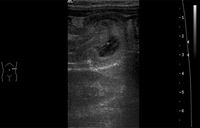

Imagem de ultrassonografia que mostra a invaginação de um segmento do intestino no segmento adjacente

BMJ Case Reports 2009; doi:10.1136/bcr.04.2009.1730; usada com permissão